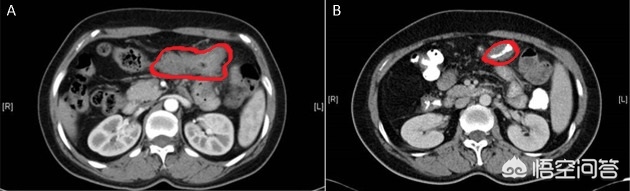

下面这张图是一个结肠癌的患者,左边是化疗前的CT,肿瘤特别大;右边是化疗后的CT,肿瘤明显缩小了。